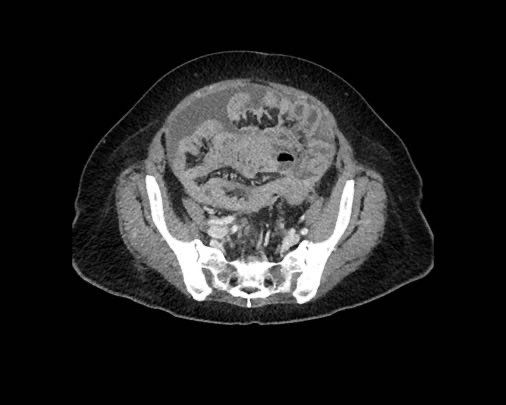

Ca lâm sàng 2

Cuộn qua các lát cắt.

Bạn có thể phát hiện tất cả các tổn thương cấy ghép phúc mạc không?

.jpeg)